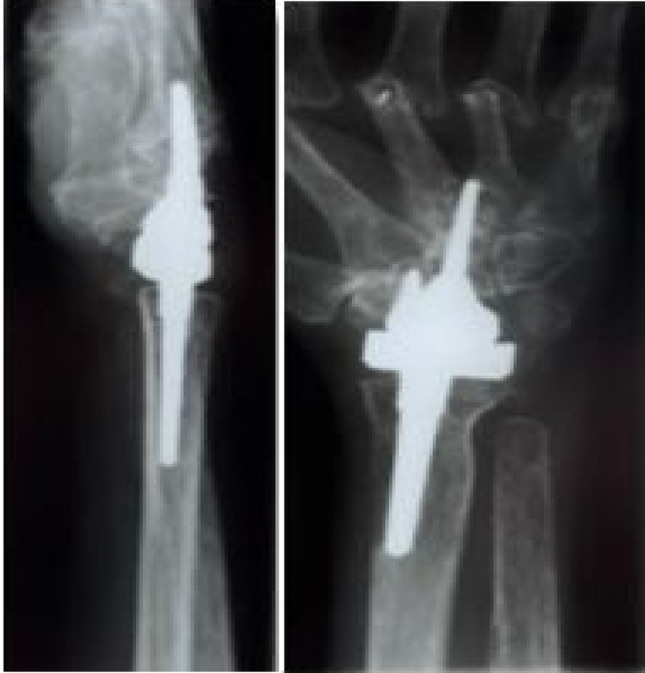

Patients/materials/methods: Between 2000 and 2011, a total of 29 total endoprostheses were implanted in 25 patients in a single centre study due to severe degenerative changes in the wrist. Of these, 22 had rheumatoid arthritis and 3 degenerative osteoarthritis. The prosthesis models BIAX (N = 13) and Universal II (N = 16) were implanted. The present study describes the mean outcome after a mean observation period of 13.8 (1.7-21.4) years for the BIAX prosthesis and 10.5 years (0.2-16.4) for the Universal II prosthesis.

Results: The probability of survival after 15 years is 60% for the BIAX prosthesis and 41% for the Universal II prosthesis. After 21 years, results are only available for the BIAX prosthesis with a value of 60%. The BIAX prosthesis showed a lower complication rate. Subjectively, 15 years postoperatively, the BIAX prosthesis showed a lower mean value in the QuickDASH score (BIAX 33.8%, Universal II 50.3%), lower results in the visual analogue pain scale under stress (BIAX: 1 point; Universal II: 3 points) with higher patient satisfaction (BIAX: 86%; Universal II: 78%).

Conclusion: In conclusion, our observations show that the BIAX prosthesis is superior to the Universal II prosthesis 15 years after surgery in terms of survival probability, complication rate and better results in satisfaction, the visual analogue pain scale and the QuickDASH score.